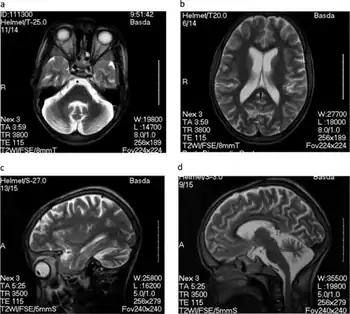

Children affected by nodding disease experience a complete and permanent stunting of growth. The growth of the brain is also stunted, leading to mental handicap. The disease is named for the characteristic, pathological nodding seizure, which often begins when the children begin to eat, or sometimes when they feel cold.[6] These seizures are brief and halt after the children stop eating or when they feel warm again. Seizures in nodding disease span a wide range of severity. Neurotoxicologist Peter Spencer, who has investigated the disease, has stated that upon presentation with food, "one or two [children] will start nodding very rapidly in a continuous, pendulous nod. A nearby child may suddenly go into a tonic–clonic seizure, while others will freeze."[7] Severe seizures can cause the child to collapse, leading to further injury.[8] Sub-clinical seizures have been identified in electroencephalograms, and MRI scans have shown brain atrophy and damage to the hippocampus and glia cells.[5]